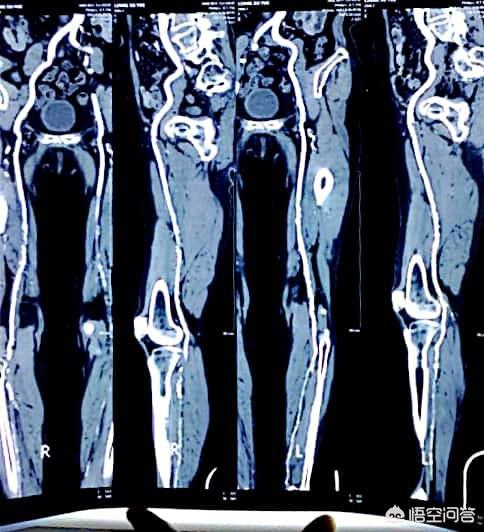

糖尿病の発生率は現在、本当に非常に高い、一般的に50歳以上、10内部の健康診断では、少なくとも1つの3つの高(高血中脂肪、高血圧、高血糖)、およびいくつかのも3つの高をすべて占めている。三高の発生と現代のペースの速い生活と人々の食習慣は大きな関係があり、次の図は糖尿病患者が登場下肢血管プラーク画像である: